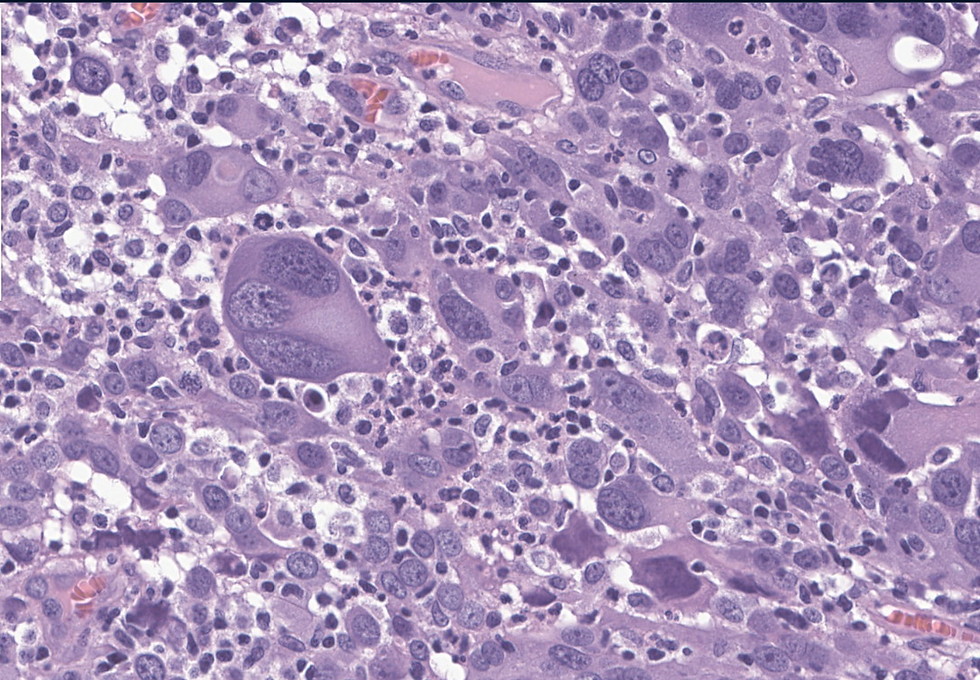

A 45-year-old female with an endometrial mass.

The correct answer is E. This is a very rare case that only described in case reports and not recognized in WHO. Immunohistochemical studies performed show tumor cells to be positive for PAX8, EMA, pankeratin and E-cadherin (patchy) while to be negative for HER2 (score 0, no staining), Napsin-A, ER, PR, GATA3, and CD68. p16 is strong diffusely positive in tumor cells. PTEN and PAX2 expressions are lost and beta catenin does not show nuclear expression. p53 staining pattern is equivocal but most areas appears to be wild type. p63 shows focal staining. Overall, the pathologic findings are consistent with mixed endometrial carcinoma with high grade endometrioid carcinoma and giant cell carcinoma components

Histological Features | - Dyshesive bizarre giant cells with atypical mitoses. - Minor components: endometrioid, serous, spindled/myxoid, and undifferentiated areas. - High mitotic index (43–211 mitoses/10 HPF). | Highly pleomorphic tumor cells with extensive mitotic activity and mesenchymal differentiation in some cases. |

Immunohistochemistry (IHC) | - Positive: Cytokeratin AE1/AE3, EMA (focal/multifocal), p16 (diffuse), hormone receptors (focal/multifocal), vimentin (2/3 cases). - Negative: E-cadherin (loss), CD68, α-FP, β-HCG, muscle markers (desmin, SMA, calponin), CD10, ERG. | - Partial loss of epithelial markers. - p53-abnormal staining in 1 case. - Mismatch repair-proficient and microsatellite-stable in all cases. - No POLE mutations detected. |